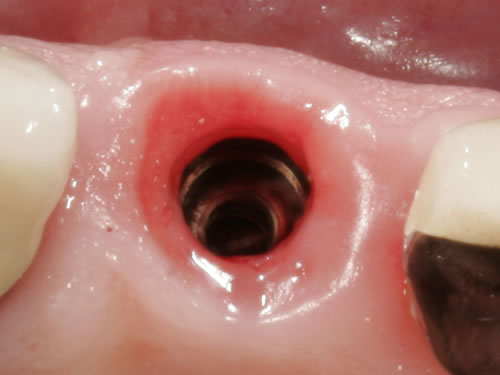

Implantate können einteilig oder mehrteilig sein. Gängiger sind mehrteilige, zusammengesetzte Implantate. Sie bestehen aus drei Teilen: dem Körper, der im Knochen verankert wird, dem Kopfteil, auf dem die künstliche Zahnkrone befestigt wird, und dem Halsteil, der genau zwischen diesen beiden Teilen liegt, im Mund also im Bereich der Schleimhaut. Nach einer Einheilungszeit des Implantatkörpers im Kieferknochen wird die Zahnkrone für jeden Menschen und für jede Kieferregion in spezieller Form und Farbe angefertigt und z.B. in einer Steck- Schraubverbindung des Implantates fixiert (Abb. 2.2).

Die meisten Implantate heilen zunächst über einige Monate unbelastet ein und werden erst dann mit einer künstlichen Zahnkrone versorgt. Die Verbindung dieser Krone mit dem Implantat erfolgt in der Regel über eine Steck-Schraubverbindung, das sich im Inneren des Implantates befindet (Abb. 2.2). Die Aufbauten werden in diesem Gewinde verschraubt oder zementiert.

Abb. 2.2: Innengeometrie eines eingesetzten Implantates.